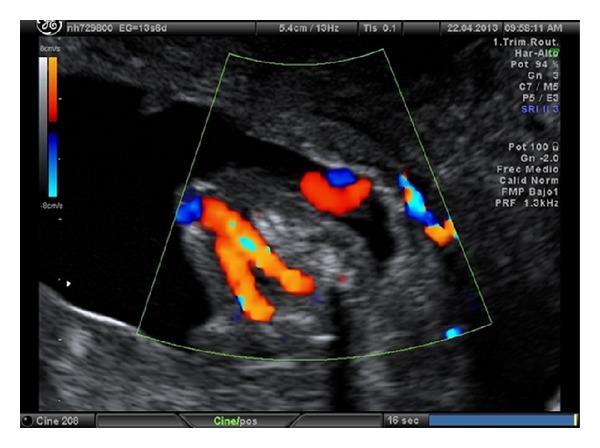

The value of a single umbilical artery (SUA) in first trimester ultrasound is not well established. The aim of our study was to determinate the relevance of diagnosis of single umbilical artery in first trimester ultrasound as an early marker suggesting the presence of malformations or associated chromosomopathies.

Prevalence of SUA was 1.1% in single pregnancies and 3.3% in twin pregnancies. Sensitivity, specificity, false positive rate, and false negative rate for the finding in the first trimester were 84.2, 99.8, 0.2, and 15.7%, respectively. 17.6% of cases had associated malformations. With an ultrasound in the 16th week most of the cases with significant fetal malformation were diagnosed.

SUA is a useful marker in the first trimester for fetal malformation pathology, as it will allow detecting a large number of cases with malformations before 20 weeks of gestation.

早孕期超声检查中单一脐动脉(SUA)的价值尚未明确确立。我们研究的目的是确定早孕期超声诊断单一脐动脉作为提示存在畸形或相关染色体病的早期标志物的相关性。

单胎妊娠中SUA的患病率为1.1%,双胎妊娠中为3.3%。早孕期该发现的敏感性、特异性、假阳性率和假阴性率分别为84.2%、99.8%、0.2%和15.7%。17.6%的病例伴有相关畸形。在孕16周进行超声检查时,大多数有严重胎儿畸形的病例得以诊断。

SUA是早孕期胎儿畸形病理学的一个有用标志物,因为它能在妊娠20周前检测出大量有畸形的病例。